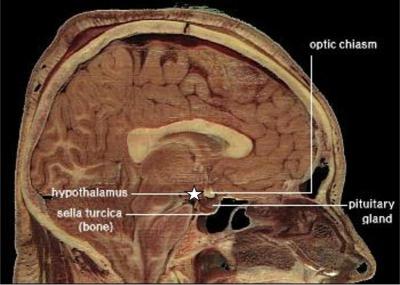

眠くなるのは脳神経の一部がホルモン(メラトニン)を分泌し、血液で体中に巡回し「休憩時間」だと告げる--下画像参照